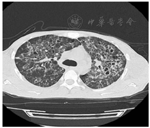

患者男,36岁,因"发现HIV抗体阳性5个月,发热、咳嗽、淋巴结肿痛3个月"于2019年3月15日入院。患者2018年11月10日确诊抗-HIV(+),查CD4+T淋巴细胞计数25个/μL,血浆HIV载量未检测,当时颈部有数枚淋巴结肿大,约1 cm×1 cm大小,无疼痛及不适,未作检查明确病因及给予特殊治疗。11月15日当地医院予拉米夫定(0.3 g/d)、替诺福韦(0.3 g/d)和依非韦伦(0.6 g/d)联合ART,12月15日患者开始出现发热,热峰40 ℃,咳嗽,少量白黏痰,颈部淋巴结进行性增大,并出现全身多处淋巴结肿痛。2019年1月10日当地医院淋巴结穿刺脓液以及肺泡灌洗液GeneXpert MTB/RIF检测阳性(无利福平耐药),诊断为"艾滋病合并肺结核、淋巴结核"。1月14日启动"异烟肼、乙胺丁醇、莫西沙星以及利福平"抗结核治疗2月余。1月15日测血浆HIV载量为200拷贝/mL。治疗后患者淋巴结肿痛仍进行性加重,咳嗽无明显好转,反复发热,遂来我院就诊。既往体健。入院体格检查:体温36.5 ℃,呼吸20次/min,脉搏120次/min,血压89/68 mmHg(1 mmHg=0.133 kPa),耳下、颌下、颈部、锁骨上、腋窝淋巴结肿大,伴触痛,部分有波动感。口腔无白斑,双肺呼吸音粗,未闻及干湿性啰音,心律齐,各瓣膜区未闻及杂音,腹软,无压痛及反跳痛,肝脾肋缘下未及肿大,肠鸣音正常,双下肢无水肿。入院后立即完善相关检查,血常规示白细胞(WBC)8.33×109/L,中性粒细胞占比0.852,血红蛋白(Hb)137 g/L,血小板360×109/L。C-反应蛋白(CRP)73.2 mg/L,降钙素原(PCT)0.12 ng/L,红细胞沉降率60 mm/1 h。CD4+T淋巴细胞计数162个/μL,血浆HIV载量低于检测值下限。血清1,3-β-D-葡聚糖104.0 pg/mL,半乳甘露聚糖0.25,隐球菌抗原阴性。痰抗酸染色阳性,GeneXpert MTB/RIF检测阳性(无利福平耐药),痰细菌培养阴性。淋巴结穿刺脓液抗酸染色阳性,GeneXpert MTB/RIF检测阳性(无利福平耐药),脓液细菌培养阴性。结核分枝杆菌耐药基因检测示异烟肼、利福平、乙胺丁醇、莫西沙星以及阿米卡星均敏感。3月15日查胸部CT:肺部弥漫性病变,示蜂窝状高密度影,支气管壁增厚,呈囊状或柱状扩张,间有多发小片状、粟粒状高密度影,边界欠清,密度欠均(图1)。患者无中枢神经系统症状,3月22日常规筛查颅脑磁共振示:颅内多发病灶,右侧脑室旁及基底节区小片状T2高信号,增强后可见结节样强化及环形强化(图2)。3月23日完善脑脊液检查:WBC 2×106个/L,总蛋白344.2 mg/L,乳酸脱氢酶(LH) 14 IU/L,葡萄糖2.8 mmol/L,氯122 mmol/L,腺苷脱氨酶0.3 U/L;抗酸染色阴性,GeneXpert MTB/RIF阴性,隐球菌抗原阴性,脑脊液细菌培养阴性;干扰素γ 12 ng/L。